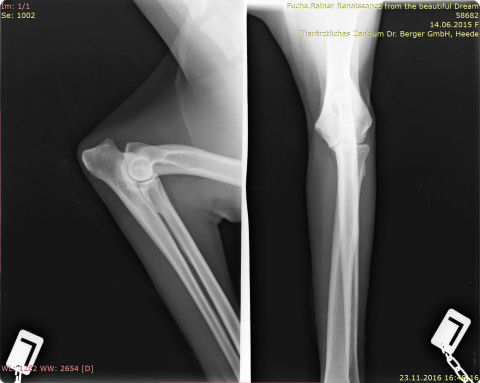

ED-Ellenbogendysplasie

roxy.ED

IMG-0004-00001-ellenbogen